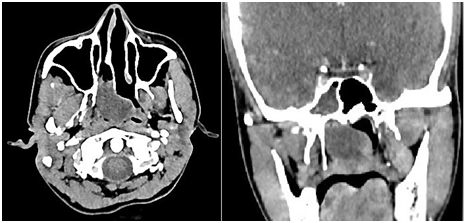

A 27year old female presented in OPD with complaint of right side nasal obstruction since two years with mouth breathing and snoring since 1year. Symptoms were gradually progressive. There were no allergic symptoms like rhinorrhea or recurrent sneezing. Her anterior rhinoscopy examination was normal, but on diagnostic endoscopic examination, pale whitish polyp was seen, which on decongestion was seen coming through right sphenoethmoid recess and nasopharynx. Left choanae was also blocked by the mass. The right and left middle meatus were clear of any pathological changes (Figure 1). Paranasal sinuses Computed tomography showed hypodense soft tissue density mass lesion with CT attenuation of 20-30 HU filling right sphenoidal sinus and extending through sphenoidal ostium, across spheno-ethmoidal recess into nasopharynx causing obstruction of both posterior choana and extending upto posterior pharyngeal wall (Figure 2). The polyp was removed via endoscopic transnasal approach. The polyp was found to attach to the junction of lateral wall and floor of sphenoid. The attachement was identified and the polyp was removed en block from its stalk and the stalk was debrided. Histopathological examination of the speci­men revealed as inflammatory polyp (Figure 3).

Figure 2 CT Paranasal sinus – axial and coronal section reveals soft tissue density filling right sphenoid sinus and extending to nasopharynx obstructing bilateral choana.